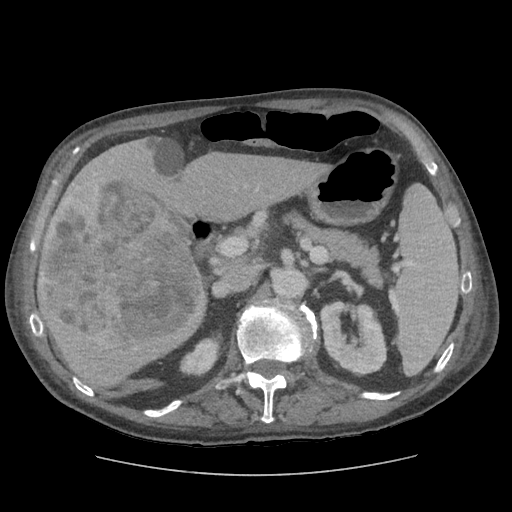

79 M with PMH of CKD, HLD, prostate cancer s/p prostatectomy + radiation presenting with feelings of fogginess, upset stomach, and diarrhea. Originally worked up at OSH, imaging concerning for a hepatic mass.

148/77 mmHg / 95 bpm / 15 breaths/min / 98.1°F / 98 ORA

sclera anicteric, no jaundice

AST 112, ALT 34, Alk Phos 202, CEA 2, CA 19-9 4